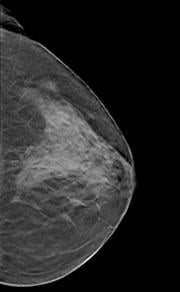

In February 2011, Hologic was the first company to obtain U.S. Food and Drug Administration (FDA) approval for 3-D breast tomosynthesis.

In clinical studies, radiologists reading 2-D mammography and 3-D breast tomosynthesis images - compared to 2-D images alone - demonstrated superior clinical performance in specificity. The combined viewing also illustrated the confidence to rule out breast cancer without recalling the patient for further study and improved sensitivity.